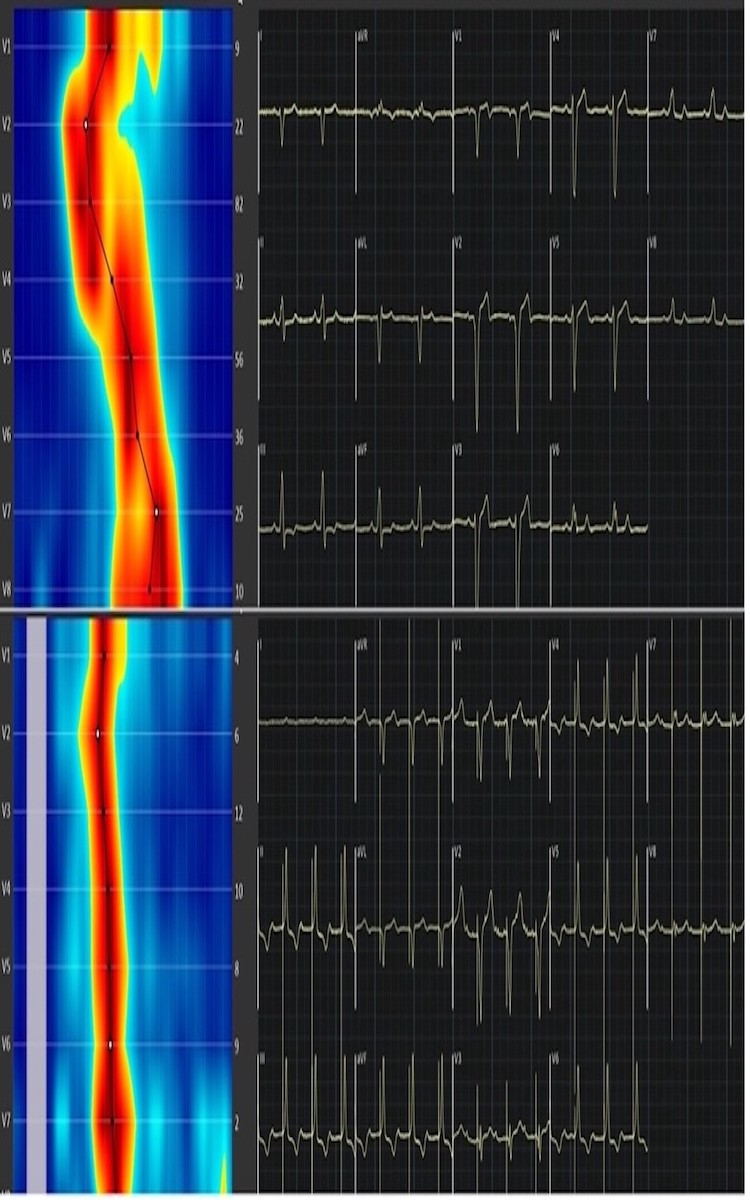

Introducción y objetivos: La estimulación hisiana (HBP) y la estimulación del área de la rama izquierda (LBBAP) han surgido como alternativas fisiológicas para corregir el bloqueo de rama izquierda (BRIHH) en la terapia de resincronización cardiaca (TRC). Sin embargo, definir la estrategia más adecuada para cada paciente sigue siendo un desafío. El electrocardiograma de ultra alta frecuencia (UHF-ECG) permite una evaluación precisa de la sincronía interventricular y constituye una herramienta útil para guiar la TRC, al mostrar en tiempo real el mapa de activación ventricular. Nuestro objetivo fue evaluar la capacidad de la estimulación fisiológica para corregir el BRIHH y analizar la mejoría en la sincronía ventricular mediante UHF-ECG.

Métodos: Se incluyeron pacientes con BRIHH sometidos a implante entre octubre de 2023 y abril de 2025. La sincronía se valoró durante el procedimiento utilizando los parámetros DYS16 y DYS18, definidos como la diferencia máxima entre los tiempos de activación ventricular medidos en V1-V6 y V1-V8, respectivamente.

Resultados: Se incluyeron 75 pacientes, de los cuales 69 (92%) fueron resincronizados mediante estimulación fisiológica (46,4% HBP y 53,6% LBBAP). Las principales indicaciones fueron BRIHH pos-TAVI (23,3%), miocardiopatía secundaria a BRIHH (21,9%) y cardiopatía isquémica con disfunción ventricular (17,8%). La edad media fue de 73,2 ± 10,2 años; 55,1% eran varones. El 64,7% recibió marcapasos y el 35,3% DAI-TRC. La FEVI media al implante fue 45,2 ± 13,6%, con un DTDVI de 53,3 ± 9,6 mm y clase funcional NYHA I-II. En 36 pacientes con disfunción ventricular, la FEVI media fue 34,1 ± 8,1%. La TRC guiada por UHF-ECG mostró una reducción significativa en DYS16 y DYS18 (p < 0,001) y en la duración y el área del QRS (p < 0,001), con una mayor reducción del QRS en HBP frente a LBBAP (p = 0,011). No hubo diferencias significativas en DYS según la técnica ni entre pacientes con o sin disfunción ventricular (p > 0,05).

UHF-ECG en tiempo real con BCRIHH basal y tras TRC con estimulación hisiana.